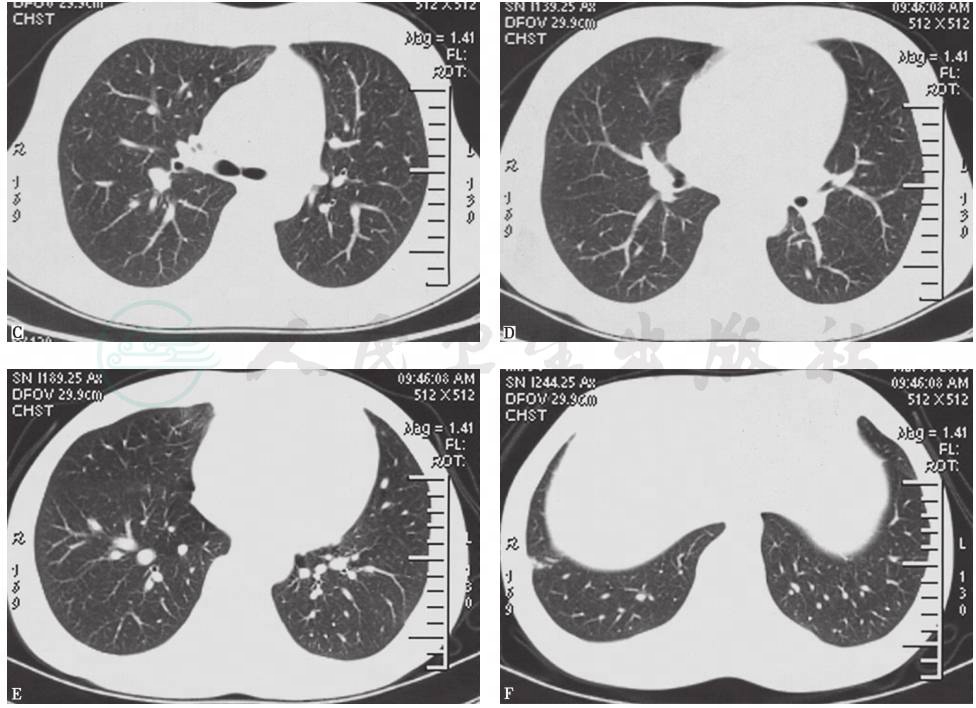

胸部CT(2014年10月16日):双肺散在小结节影,未见结节空洞改变、肺门和纵隔淋巴结肿大和胸腔积液征象(图1)。

胸部CT(2014年12月23日):双肺散在结节影,边界模糊,右肺上叶见薄壁空洞影,未见肺门和纵隔淋巴结肿大,未见双侧胸膜积液(图2)。

图1 胸部CT表现(2014-10-16)

图2 胸部CT表现(2014-12-23)

胸部CT(2015年1月6日):双肺多发高密度影,右下肺明显,双侧少量胸腔积液,肺动脉增宽,纵隔未见肿大淋巴结影(图3)。

图3 胸部CT表现(2015-01-06)

胸部CT(2015年1月23日):双肺内散在斑片状高密度影较前有所吸收,右肺下叶斑片影可见小空洞形成,双侧胸腔积液吸收、好转(图4)。

胸部CT(2015年3月1日):仅见右肺小结节影、索条影,右下肺近肋膈角处高密度楔形影,未见胸腔积液(图5)。

图4 胸部CT表现(2015-01-23)

图5 胸部CT表现(2015-03-01)